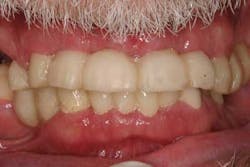

Case study A 58-year-old male with a noncontributory medical history presented to a private practice for a complete rehabilitation of his dentition due to years of bruxism and parafunction. (Fig. 1) After surgical and restorative consultations, a treatment plan was fabricated. The treatment plan included restoring his lost vertical dimension, restoring his natural dentition with porcelain-fused-to-metal full-coverage crowns, and replacing his lost posterior teeth with dental implants. After his vertical dimension was restored with an acrylic bite plate to a position harmonious with TMJ function, crown-lengthening surgery was performed. (Fig. 2)Fig. 2 Six weeks after, the teeth were temporized to develop soft tissue margins/interdental papillae. (Figs. 3 and 3a) The patient was kept in temporaries for three months, during which time an implant was placed in site No. 19. Both the natural dentition and the implant were completed at the same time, three months after implant placement. (Fig. 4) Because of the patient’s occlusal issues, the implant was screw-retained, and the patient was given a maxillary night guard. Three weeks after insertion, the patient presented with a loose abutment screw. The dentist tightened the screw and sent the patient home. This cycle was repeated two more times until the patient presented again with a loose crown, but this time, a fracture implant screw. The dentist attempted to remove the screw with a Cavitron and drilling the implant screw out to release preload, but to no avail. The case was then referred to my office for implant removal.